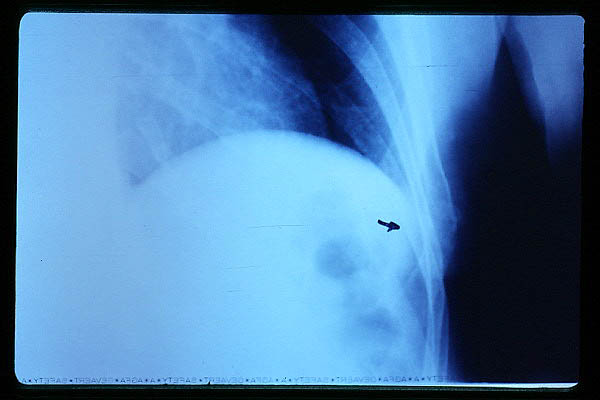

Hernia de hiato gigante.

Nivel hidroaéreo en hernia de hiato gigante.